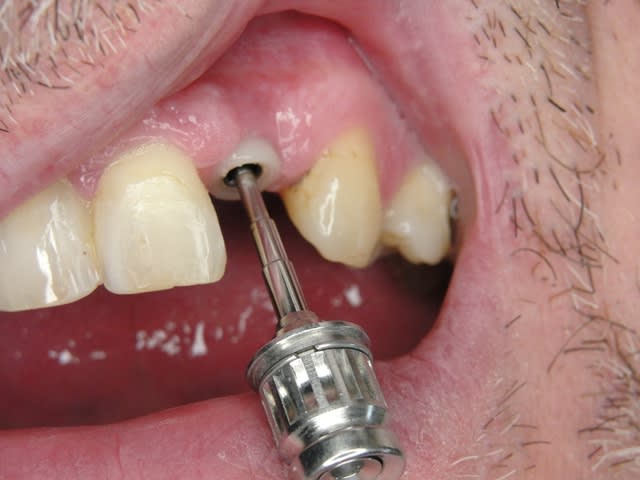

Sur la photo 5 on voit que je prépare surtout le titane de l´implant, le titane ne donne pas beaucoup du chaud quand il est préparé avec l´eau (pas comme aluminium par exemple).

Le dernier photo cela montre le système des Prep Caps :

il y a deux point de réferences en rouge c´est où finit la prep caps et en jaune où commence la prep caps (à la base) .

De retour en allemagne! Alors j ai des vidéos pour la taille du titane/ zircone mais je ne peux pas les modifier comme sur les power point pour enlever les noms...

Sur la video en bas au milieu on voit le prép cap la fin du cas pour la prothétique c est la page 8 la 6 eme video... Il doit y en avoir des autres sur comment on taille mais sur les 200 je n arrive pas à trouver.....